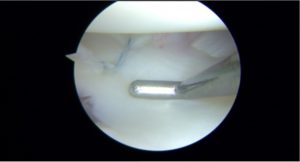

All inside meniscal fixation using mainly two FasT-Fix® devices (Smith and Nephew)

The diagnosis of hypermobile lateral meniscus is a clinical diagnosis only confirmed during the arthroscopy.